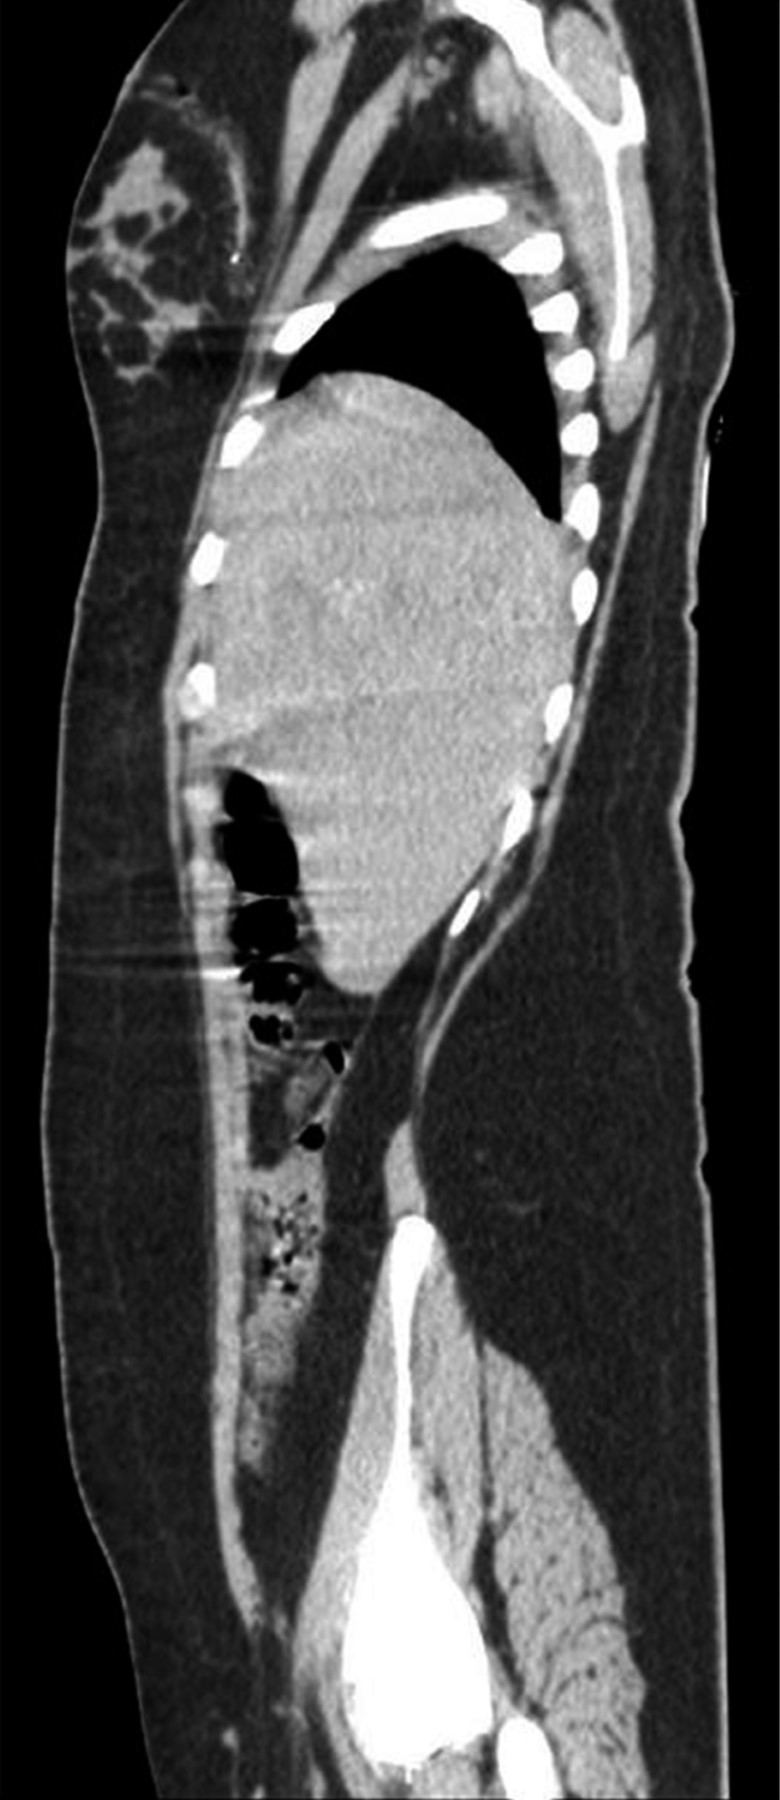

En la exploración física, sus signos vitales fueron los siguientes: frecuencia cardiaca: 74 latidos/minuto; tensión arterial: 98/67 mmHg; frecuencia respiratoria: 19/minuto, temperatura de 36 °C y saturación de oxígeno: 98%. En tórax presentaba un orificio de entrada de PAF en el cuadrante superior externo de la mama derecha (Figura 1), los campos pulmonares estaban bien ventilados. El abdomen era plano, con peristalsis, blando y sin dolor a la palpación. La biometría hemática reportó lo siguiente: hemoglobina: 12.8 g/dl, hematocrito 36.4% y leucocitos: 6,400/ml. La radiografía de tórax descartó neumotórax (Figura 2). Una TC de tórax y abdomen mostró un cuerpo extraño metálico alojado en la línea parasagital derecha a nivel de la doceava vértebra torácica (Figura 3), sin lesión pulmonar ni diafragmática (Figuras 4 y 5); en abdomen se observó un trayecto por PAF con lesión hepática grado IV de 12 cm por 2.3 cm en los segmentos IV, VII y VIII de Couinaud (Figura 5), líquido libre escaso, sin lesión de ningún otro órgano (Figuras 3, 5 y 6). Veinticuatro horas después se le realizó una TC de control, evidenciando la lesión hepática sin colección subcapsular ni extravasación activa a la aplicación del medio de contraste, sin aumento del líquido libre. Ante la correlación de estos hallazgos con la estabilidad clínica, se egresó a la paciente al cuarto día de su ingreso. Sin complicaciones un mes después de su alta.

Figura 4